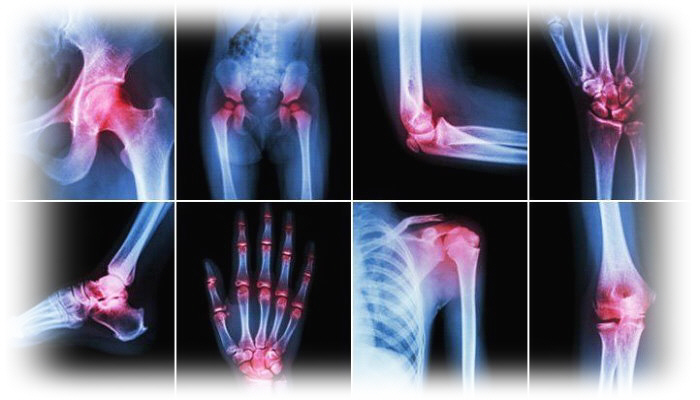

هل هناك أكثر من مفصل واحد مصاب؟